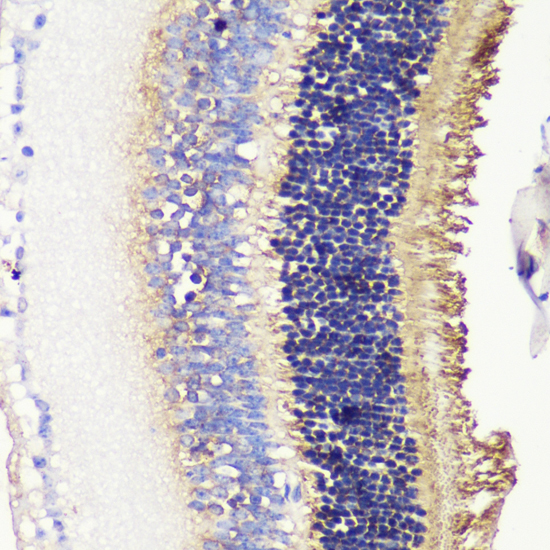

Immunohistochemistry of paraffin-embedded rat retina using PDC antibody.

Immunohistochemistry of paraffin-embedded mouse retina using PDC antibody.